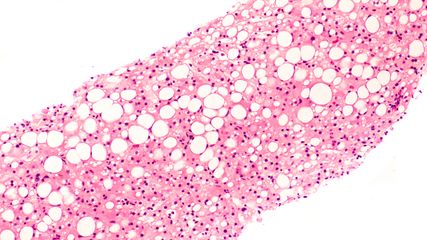

Die Leberzirrhose ist die häufigste Ursache der portalen Hypertonie.1 Einer epidemiologischen Studie zufolge nimmt die Prävalenz der Leberzirrhose in europäischen Ländern weiter zu. Je nach Land hängt der Anstieg mit schädlichem Alkoholkonsum oder Hepatitisvirus-Epidemien zusammen. Aber auch Länder mit historisch niedrigen Raten dürften in Zukunft vermehrt Leberzirrhosen verzeichnen. Dies, weil in der westlichen Bevölkerung die Adipositas zunimmt und dadurch das Risiko für Metabolismus-assoziierte steatotische Lebererkrankungen (MASLD) steigt, so die Schlussfolgerung der Studie.2

Die portale Hypertonie kann schwerwiegende bis lebensbedrohliche Komplikationen verursachen. Dazu gehören: Aszites, Ösophagus- und Fundusvarizen – und damit ein hohes Risiko gastrointestinaler Blutungen –, Splenomegalie und hepatische Enzephalopathie. Im schlimmsten Fall müssen bei Betroffenen lebenserhaltende Massnahmen innert kürzester Zeit eingeleitet werden.3,4 Für die Behandlung der portalen Hypertonie gilt es also, den Druck in der Pfortader und die Risiken von Komplikationen so weit zu senken, dass der Zustand stabilisiert wird (Abb. 1). Wie das gemacht wird, zeigte De Gottardi in seinem Vortrag auf.